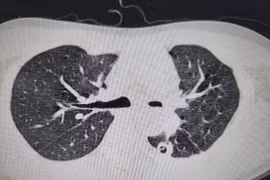

Lao phổi là bệnh có thể để lại di chứng, dẫn đến những vấn đề sức khỏe lâu dài dù việc chữa trị căn bệnh này đã có nhiều tiến bộ. Ước tính có khoảng ⅕ số người sau điều trị bệnh lao phổi gặp di chứng.

Chăm sóc và theo dõi sau khi hoàn thành điều trị lao thường bị bỏ qua. Sau khi hoàn thành điều trị, mặc dù cơ thể đã tiêu diệt hoàn toàn vi khuẩn lao nhưng vẫn có thể để lại những triệu chứng hoặc di chứng do lao hoặc thuốc.